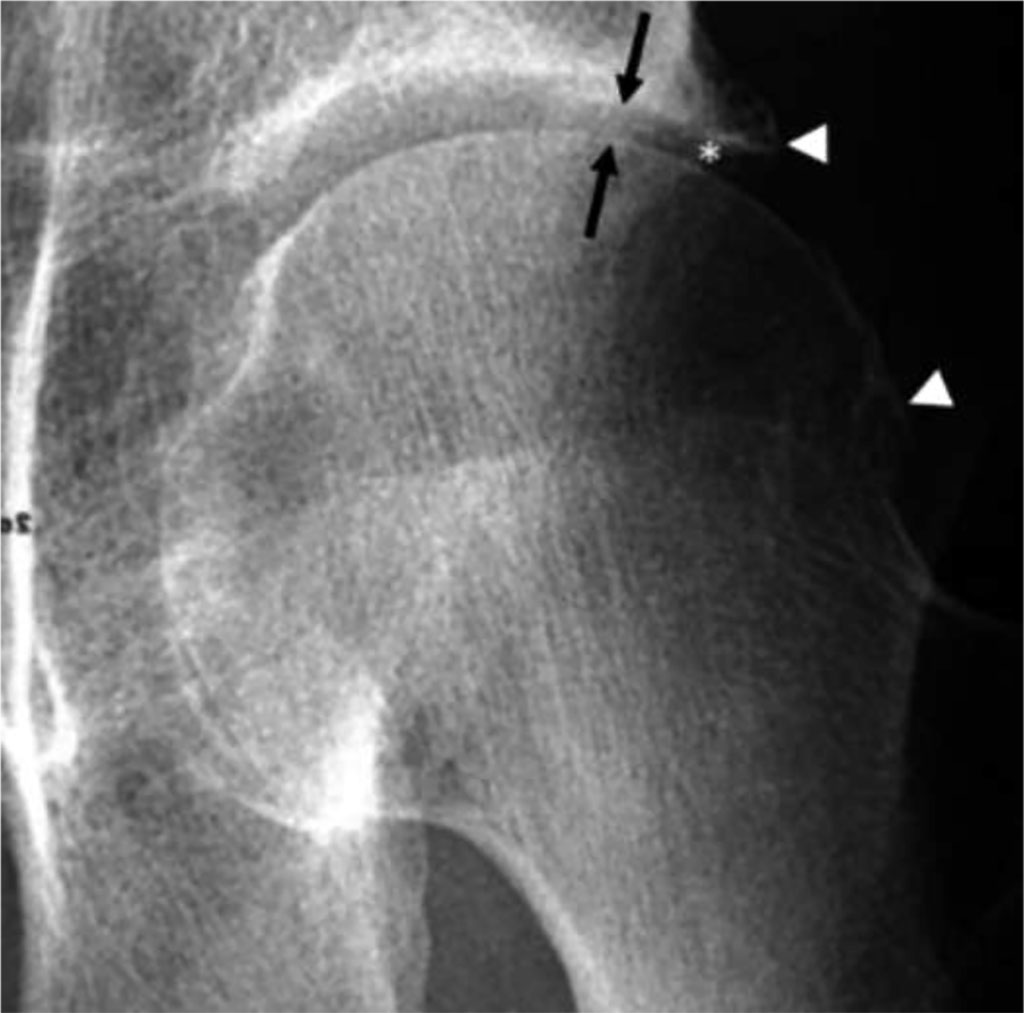

Fig 2. Osteoarthritis of the left hip. AP RTG demonstrates lateral joint space narrowing (arrows) and marginal osteophytes (arrowheads) [7].

Degenerative joint disease is characterized by pain, which can be observed in tests such as flexion, extension, and internal rotation. Other symptoms include stiffness and decreased mobility, which make it difficult for the patient to perform daily activities. The etiology is associated with damage to the articular cartilage; disturbances in degradation and synthesis [5]. Studies show that risk factors for this disease include obesity, female gender, and age. It is believed that psychological disorders such as depression, anxiety disorders, and psychosis also play a role in the pathogenesis [6]. The diagnosis of degenerative joint disease of the hip is based on clinical symptoms and imaging tests. In the initial phase of the disease, magnetic resonance imaging (MRI) may be used to show changes in the articular cartilage. However, the most important imaging test for diagnosis is the anterior-posterior (AP) X-ray. Key to diagnosis is the narrowing of the joint space to below 2mm and the presence of osteophytes, which are bony outgrowths resulting from bone tissue overgrowth [7]. In treatment, rehabilitation, pain relievers, commonly NSAIDs, and surgical methods such as THA [8] or arthroscopy are used. Arthroscopy is an effective technique in treating femoroacetabular impingement (FAI) and rim injuries, which are one of the causes of degenerative hip joint disease [9].